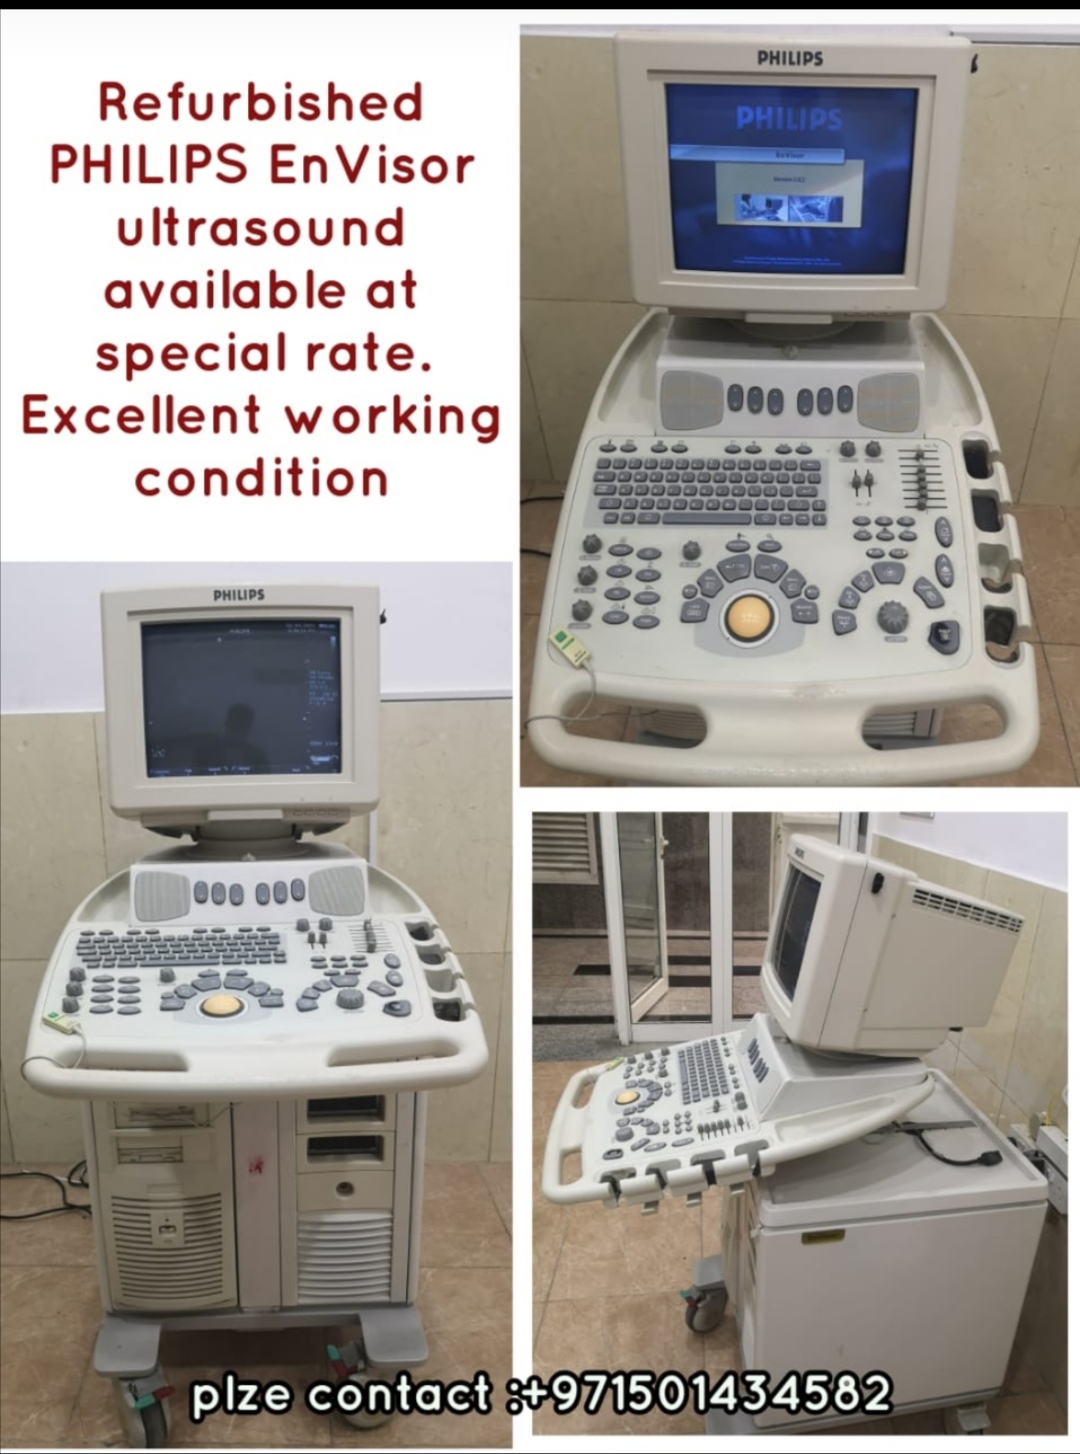

Refurbished PHILIPS EnVisor ultrasound

Refurbished PHILIPS EnVisor ultrasound